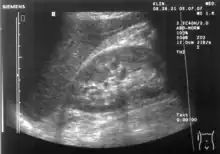

A normal ultrasonographic view of Morison's pouch. The bright line is the capsule of the kidney; there is no fluid present and hence no visible space.

Ultrasonographic view of the abdomen demonstrating fluid within Morison's pouch